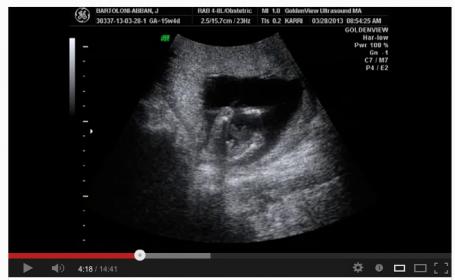

So I don't have pics from today but I do have a video that is long but if you have time and feel like trying to see if you can tell what baby is please take a look. Tech was not able to determine gender because baby was all over place and legs crossed.

http://youtu.be/dGVw-kcT5wE

I watched the video around 4:18 ish I see boy bits!!!

Thanks Thorz..I also thought I saw boy bits but the tech for some reason could not determine and I have to go back in a week.

I agree with thorz I took a screen shot

Attachment 10002

Thanks navywife. Perfect pic wish I knew why tech couldn't determine gender.